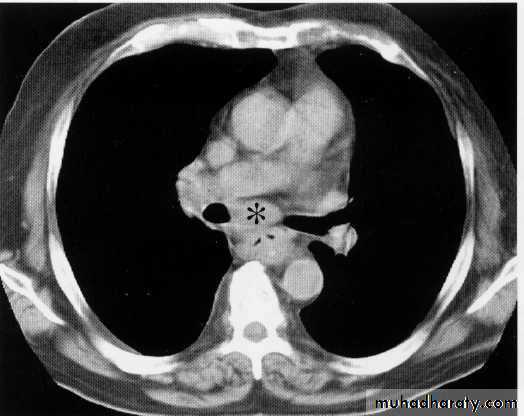

Ct scan carinal LAP